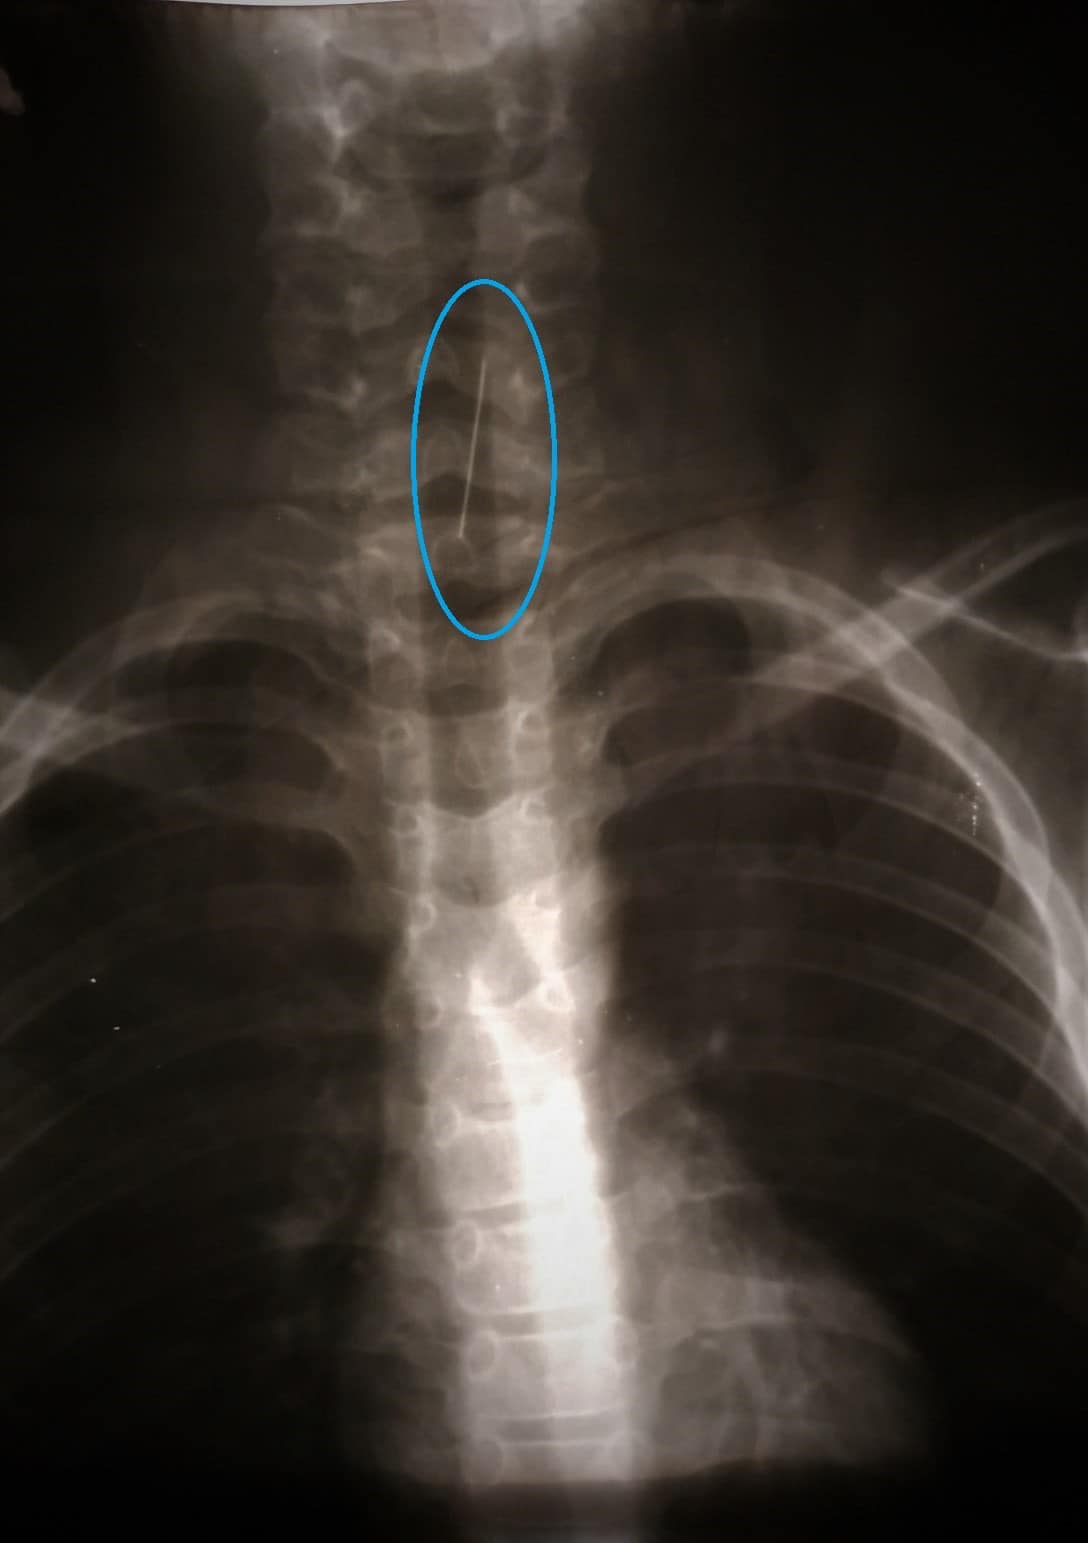

В Днепре в больницу попал ребенок с булавкой в дыхательных путях. В частности, шпилька успела подколоться к трахее, что затруднило ее извлечение.

Так, ребенок проглотил булавку, и во время диагностического эндоскопического исследования оказалось, что она подкололась к трахее.

В частности, доставали посторонний предмет целая бригада медиков. Сначала они пытались ее достать с помощью "петли", но шпилька начала "мигрировать" вниз дыхательными путями. Там до правого бронха она підкололася к сегментарной бронхи и через неосторожное движение могло стать причиной осложнений.

По словам медиков, они просчитали разные варианты развития событий и приняли крайне нестандартное решение, а именно ввести через жесткий бронхоскоп гибкий бронхоскоп.

Поэтому после некоторых осторожных и медленных манипуляций им удалось удалить злосчастную шпильку из дыхательных путей маленького пациента и почти не травмируя слизистую ни бронха, ни трахеи.